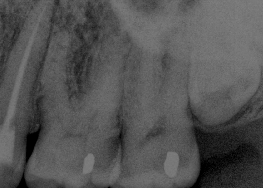

Bruxir Crown, Hairline Fracture, Prepared Canals, Postop Root Canal